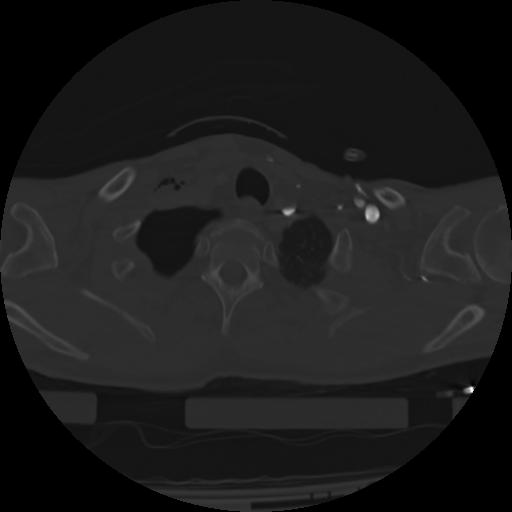

21 ANGIO,CE,Axial,3.0,ANGIO,,